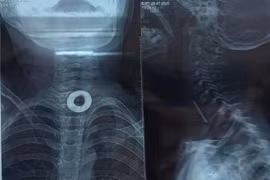

(khoahocdoisong.vn) - Các bác sĩ Bệnh viện Nhi đồng 1 TPHCM vừa tiến hành nội soi vừa mổ mở cho một bệnh nhi để giải phóng đường thở khỏi chiếc khóa dây kéo bằng kim loại có kích thước 20*4mm.